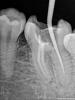

Денис481 Опубликовано 28 июля, 2012 Поделиться Опубликовано 28 июля, 2012 45 зуб протейперами обработал,на снимке перед пломбировкой(справа) все хорошо,а запломбировал чуть не дошел до апекса,как вы думаете грозит зубу что то или нет? просто переживаю как то только начинаю работать хочется чтоб все идеально было как в учебнике,хотя у меня есть во рту зуб который намного хуже пролечен там до апекса не дошли мм 2 но тфу тфу 2 года полет нормальный,а тут я померил 0.4 не дошел.....обидно что канал хороший а так получилось,кстати пломбировал ah+ c гуттой конусной под протейпер Ссылка на комментарий

Денис481 Опубликовано 28 июля, 2012 Автор Поделиться Опубликовано 28 июля, 2012 одним штифтом конусным силлер ah +,сначала наполнителем чуть по стенкам потом нанес на штифт и в канал,щас листал литературу там написано что надо не доходить до рентген верхушки при витальной экстерпации 1.5 мм и при девитальной 1мм так что выходит правильно все)))) Ссылка на комментарий